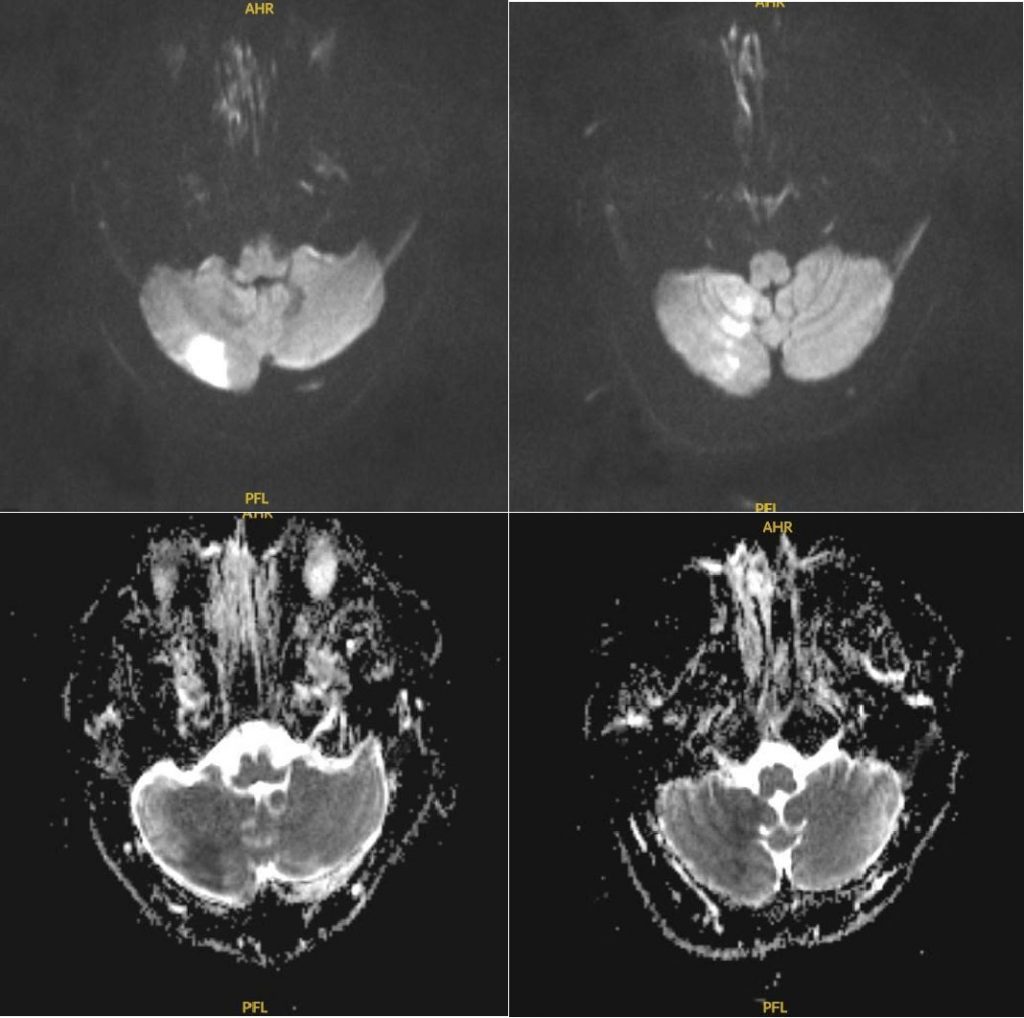

Ngay lập tức, người bệnh được tiến hành chụp MRI, kết quả xác định có vùng nhồi máu tiểu não bên phải. Bệnh nhân được kiểm soát huyết áp, tiêm thuốc tiêu sợi huyết (rTPA) qua đường tĩnh mạch có tác dụng tái thông mạch máu đang bị tắc nghẽn, giúp cấp máu và oxy kịp thời cho các tế bào não đang có nguy cơ bị tổn thương nghiêm trọng.

Hình chụp MRI của bệnh nhân trong khi đá banh bị đột quỵ